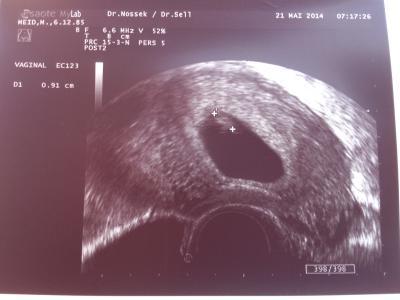

So, heute morgen beim fa gewesen . Und ich habe das schlagen sehen!!! Unser Krümmel scheint zwar noch etwas zu klein zu sein, aber ob deret verändert wird, bekomme ich erst nächstes mal ggesagt! Aber sonst alles fit, bis auf meinen Pilz, den ich nicht recht loswerde. Ach ja, bin rechnerisch heute 7+5 und es war Ca 1 cm groß! Wie sieht bei euch aus? Nächster Termin ist in vier Wochen! Lg

Bild zu heute war fa Termin - Forum für Januar - Mamis